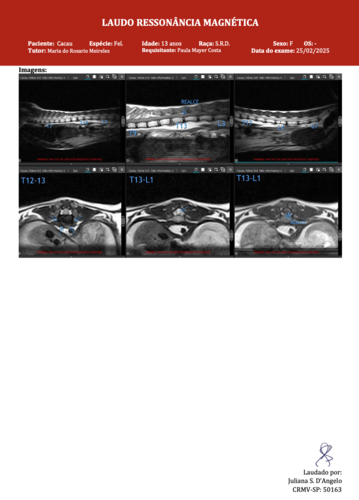

Essa é a Cacau, uma gatinha extremamente dócil que está lutando por sua vida. Há três dias, ela foi internada com paralisia nas patas, e desde então tem passado por diversos exames para descobrir a causa do problema. Infelizmente, ainda não sabemos ao certo o que está acontecendo, e enquanto os veterinários seguem investigando, ela recebe tratamento neurológico intensivo.